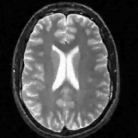

The reconstructions of a 256×256256256256\times 256 brain image from its radial samples acquired with a 40 spoke trajectory are shown in Fig. 6. The measurements are corrupted with zero mean complex Gaussian noise of standard deviation σ=18.8𝜎18.8\sigma=18.8. All methods result in loss of subtle image features since the acceleration factor and the noise level are high. We observe that the NLS scheme provides better recovery than the competing methods. The quantitative results in this setting for various MR images are shown in the bottom section of Table IV. We observe that the SNR improvement offered by NLS over the other methods are not as high as in the previous cases, mainly due to the considerable noise in the data and the high acceleration.

Refer to caption

(a) Original

(b) DLMRI,SNR=17.46

(c) TV,SNR=17.43

(d) NLS,SNR=18.46

(e) Sampling pattern

(f) DLMRI error

(g) TV error

(h) NLS error

Figure 6: Comparison of the algorithms in the presence of noise. We consider the recovery of a 256×256256256256\times 256 original MRI brain image from its radial trajectory with 40 spokes, contaminated by Gaussian noise with standard deviation σ=18.8𝜎18.8\sigma=18.8. The error images are magnified by a scale of 5 fold for the best visibility. This is a challenging case due to the high undersampling factor and high measurement noise. We observe that the NLS scheme provides the best overall reconstructions.